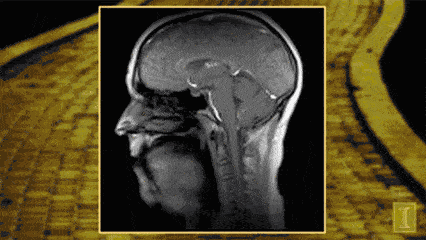

會厭,位於人體舌根部。急性會厭炎是喉科急重症之壹,主要表現為會厭高度水腫。

對於嚴重的急性會厭炎患者,留院觀察是必須的。氣管切開包都必須備在病人床邊。

急性會厭炎導致的喉梗阻,可以說是耳鼻喉科最緊急的急診了。